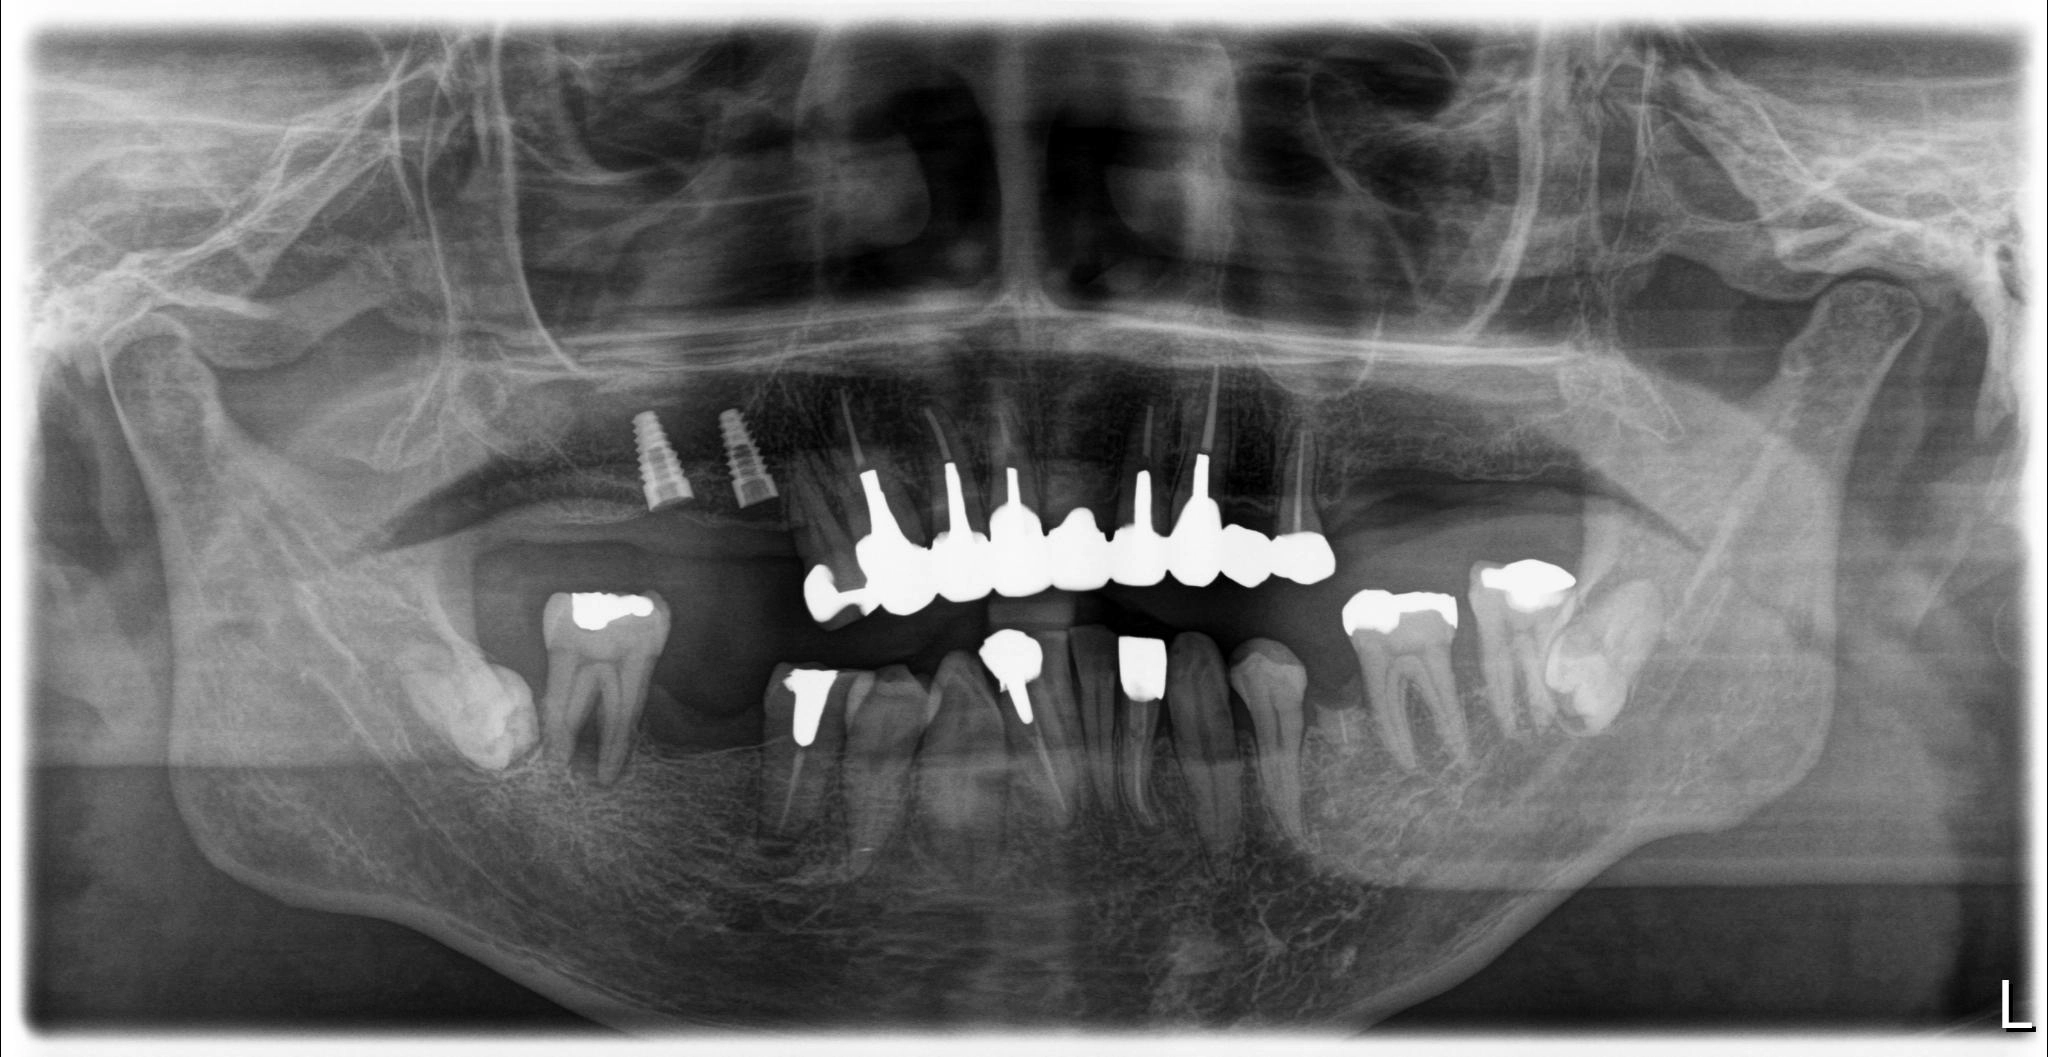

福岡県 49歳(男性)

「長年の口元の不安が負担」

術前

術後

内容 :上下顎オールオン4ザイゴマ0

費用 :4,989,600円

※モニター価格

期間 :半年

リスク:出血・腫れ・痺れ・痛み

他院でインプラント治療を行っていましたが突然閉院となり、治療が中断されてしまいました。噛み合わせや歯並びに深刻な悩みを抱えることになり、口元の不安が負担になっていました。

相談の中でわずか1日で固定式の歯が入るスピード感に大きな魅力を感じました。

「ここなら長年の悩みが無くなるかもしれない」と感じ、手術を受ける決断をしました。

手術当日に歯が入り、その即時性に深く満足しています。これまでは人前で笑えないことが最大の悩みでしたが、これからは笑顔が増えていきそうです。